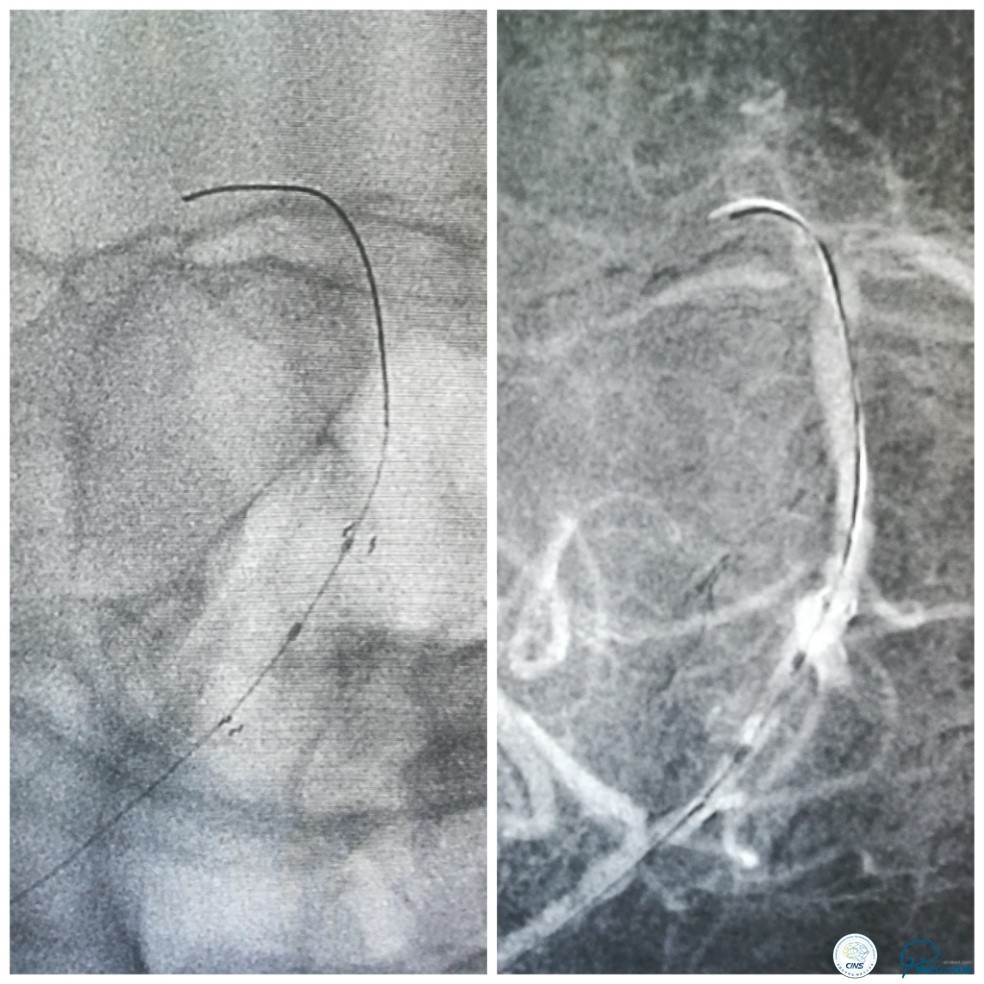

缓慢回撤6F导引导管至锁骨下动脉,造影显示右椎V1段支架无移位,前向血流正常(图17)。

图17